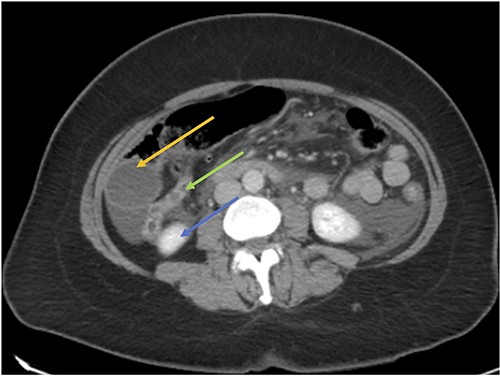

Computerized tomography scan of the abdomen showed an acute cholecystitis as well as radiological features of an acute pancreatitis. There was no pancreatic necrosis, abscess or choledocholithiasis.

CT axial view showing the appendix (green arrow) inferior to the gallbladder (orange arrow) and superior to the right kidney (blue arrow).